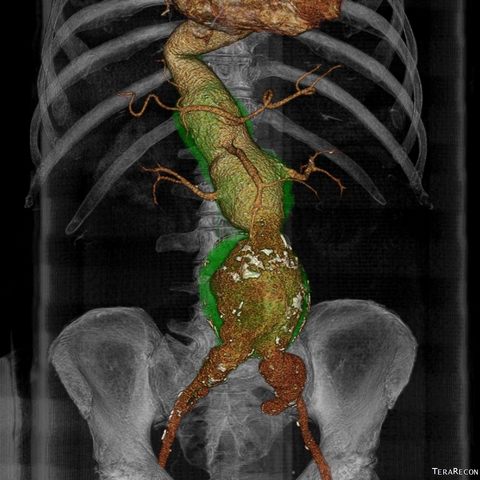

“INTERVENTO COMPLESSO”. “L’intervento che abbiamo eseguito – spiega Alberti – si è rivelato molto complesso, non solo per le dimensioni dell’aneurisma, 5 volte il diametro normale, ma anche per l’estensione all’aorta nel suo tratto toracico e addominale, coinvolgendo quindi le arterie che portano il sangue al fegato, all’intestino e ai reni. Per escludere l’aneurisma dalla circolazione, ed evitare il rischio di rottura imminente, abbiamo utilizzato dei piccoli accessi chirurgici. Tramite questi è stato possibile posizionare in aorta una protesi caratterizzata dalla presenza di fori per le arterie viscerali che sono state rivascolarizzate attraverso il posizionamento di stent”.

LE MODALITA’ DI INTERVENTO. “Per eseguire l’intervento – commenta il direttore generale della Asl di Viterbo, Daniela Donetti –sono stati utilizzati dei sistemi avanzati di ricostruzione delle immagini radiologiche preoperatorie che hanno permesso di selezionare le corrette dimensioni dei materiali, pianificare le migliori strategie e garantire il successo della procedura. Tutto il percorso diagnostico-terapeutico del paziente è stato portato avanti, in maniera sinergica, dalle unità operative di Chirurgia vascolare e Radiologia interventistica dell’ospedale Belcolle, attraverso un moderno approccio multidisciplinare. Prosegue, dunque, il percorso avviato dalla Chirurgia vascolare di Belcolle verso un continuo e progressivo incremento nell’utilizzo delle più moderne tecnologie, al fine di migliorare le capacità di cura e di rispondere adeguatamente a questi specifici bisogni di salute”.

(Dida foto Ricostruzione tridimensionale dell’aneurisma dell’aorta toracica e addominale) (agg. 21/03 ore 19)